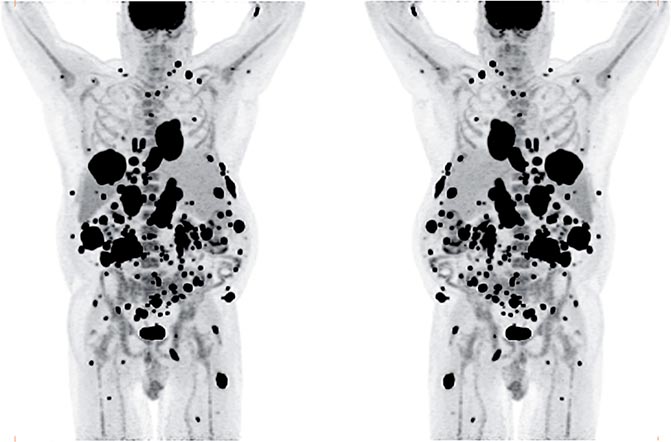

The patient was referred for 18F-FDG-PET/CT the next day to further evaluate the disease extent. A whole-body PET/CT was performed 60 min after the intravenous injection of 629 MBq (17 mCi) 18F-FDG. The study showed multiple hypermetabolic foci throughout the body (Figure 1). There was a large soft tissue mass in the right lower lobe with increased 18F-FDG uptake; the maximum standardized uptake value (SUVmax) of this lesion was 38.0. Also, there were multiple hypermetabolic nodules in the thyroid, gastric mucosa, pancreas, and both the adrenals. Both kidneys contained exophytic lesions with increased 18F-FDG uptake (Figure 2). A circumferential soft tissue mass in the esophagus was hypermetabolic as well. Additional FDG-avid nodules and masses were also found in the peritoneum and omentum; the largest of these had a SUVmax of 68.0. Intense FDG uptake was observed in multiple subcutaneous and intramuscular nodules throughout the body, some of which were thought to represent lymph nodes. Brain magnetic resonance imaging was performed on the same day, which revealed five metastatic lesions measuring up to 1.5 cm in the left frontal lobe, anterior right parietal lobe, and right temporal lobe. At this point, there were multiple candidate lesions for the primary malignancy, such as lung, esophagus, melanoma, or an aggressive lymphoma.

Fig 1

Figure 1. Maximum intensity projection (MIP) images in anterior and posterior views of the 18F-FDG PET/CT images showing multiple hypermetabolic foci of increased FDG uptake throughout the body, most likely representing widespread metastatic disease.